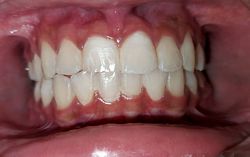

Case No: 14

Orthodontics/Adult Orthodontics/ Adjunctive Orthodontics Malocclusion Type: Missing Upper Left Central Incisor.

Mechanics: Movement of upper central incisor to upper lateral incisor position and converting the upper right lateral incisor to upper right central incisor by relieving the crowding.

Intra-oral : Pre & Post-treatment : Frontal View

Inta-oral : Pre & Post-treatment : Occlusal View